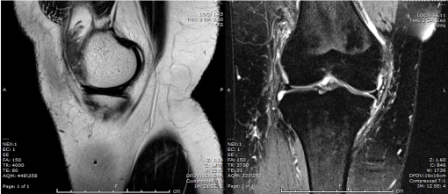

MRI of the knee was performed.

Q. What is your opinion on the MRI scan?

• Knee joint effusion

• Hypertrophy of the synovium

• Normal cartilage and bony outline. Meniscus, ACL, and PCL were intact.

MRI is the best approach showing the masslike synovial proliferation with lobulated margins, with low signal intensity and "blooming" artifact on gradient echo due to haemosiderin deposition [4].